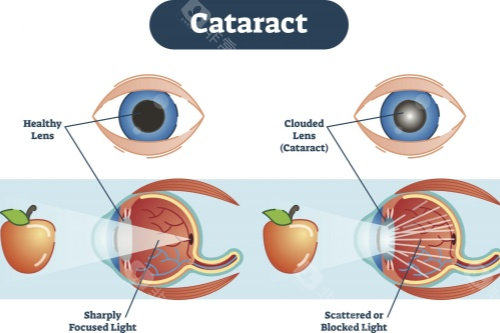

医学层面,申请者需经专科诊断确诊为白内障,且裸眼视力≤0.3或矫正视力<0.5,这一标准是判断手术必要性的核心依据。同时需排除相关禁忌症,例如活动性眼部感染、未控制的全身性疾病等。